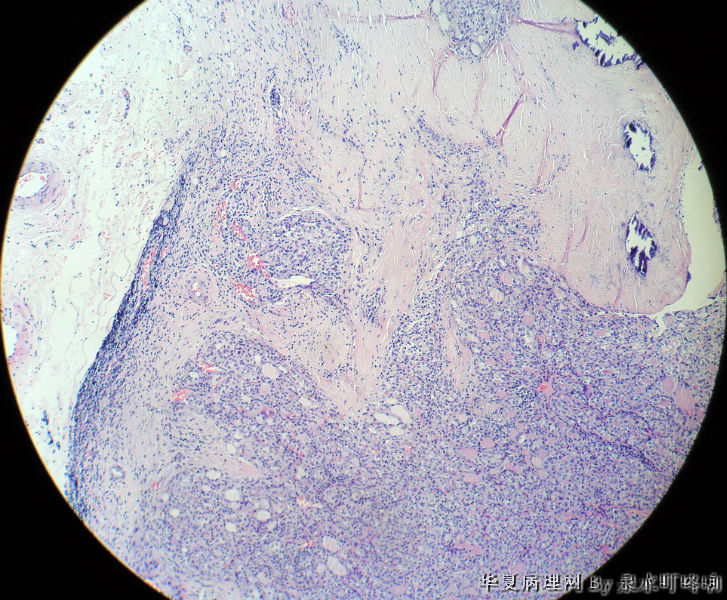

120212,女,55岁,左颈部肿物七年余。

大体:灰白肿物一个,大小约2.1×1.5×1.3厘米。表面光滑,包膜完整,切面灰白,部分包膜有钙化。

与手术医生沟通,肿物位于左颈部靠近甲状腺部位,比较浅(门诊手术),手术医生认为是淋巴结部位。

厚包膜、蕈状浸润----滤泡癌。

甲状腺滤泡性肿瘤,可见包膜及血管侵犯,考虑滤泡癌。

甲状腺滤泡状癌,有包膜浸润及血管内瘤栓